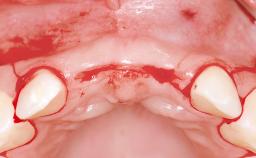

Replacement of Four Incisors with a Fixed Partial Denture on Two Narrow-Neck Implants after Implant Failure

| Soft Tissue Anatomy | Intact | Defective | |

| Bone Volume | Horizontally and vertically sufficient | Horizontally deficient | Deficient vertically or deficient vertically AND horizontally |

| Bone Volume | Deficient vertically or deficient vertically AND horizontally |

| Soft Tissue Contour and Volume | Significantly deficient |